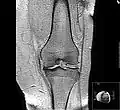

Diagnosis is made with reasonable certainty based on history and clinical examination.[52][53] X-rays may confirm the diagnosis. The typical changes seen on X-ray include: joint space narrowing, subchondral sclerosis (increased bone formation around the joint), subchondral cyst formation, and osteophytes.[54] Plain films may not correlate with the findings on physical examination or with the degree of pain.[55]

MRI of osteoarthritis in the knee, with characteristic narrowing of the joint space

Primary osteoarthritis of the left knee. Note the osteophytes, narrowing of the joint space (arrow), and increased subchondral bone density (arrow).